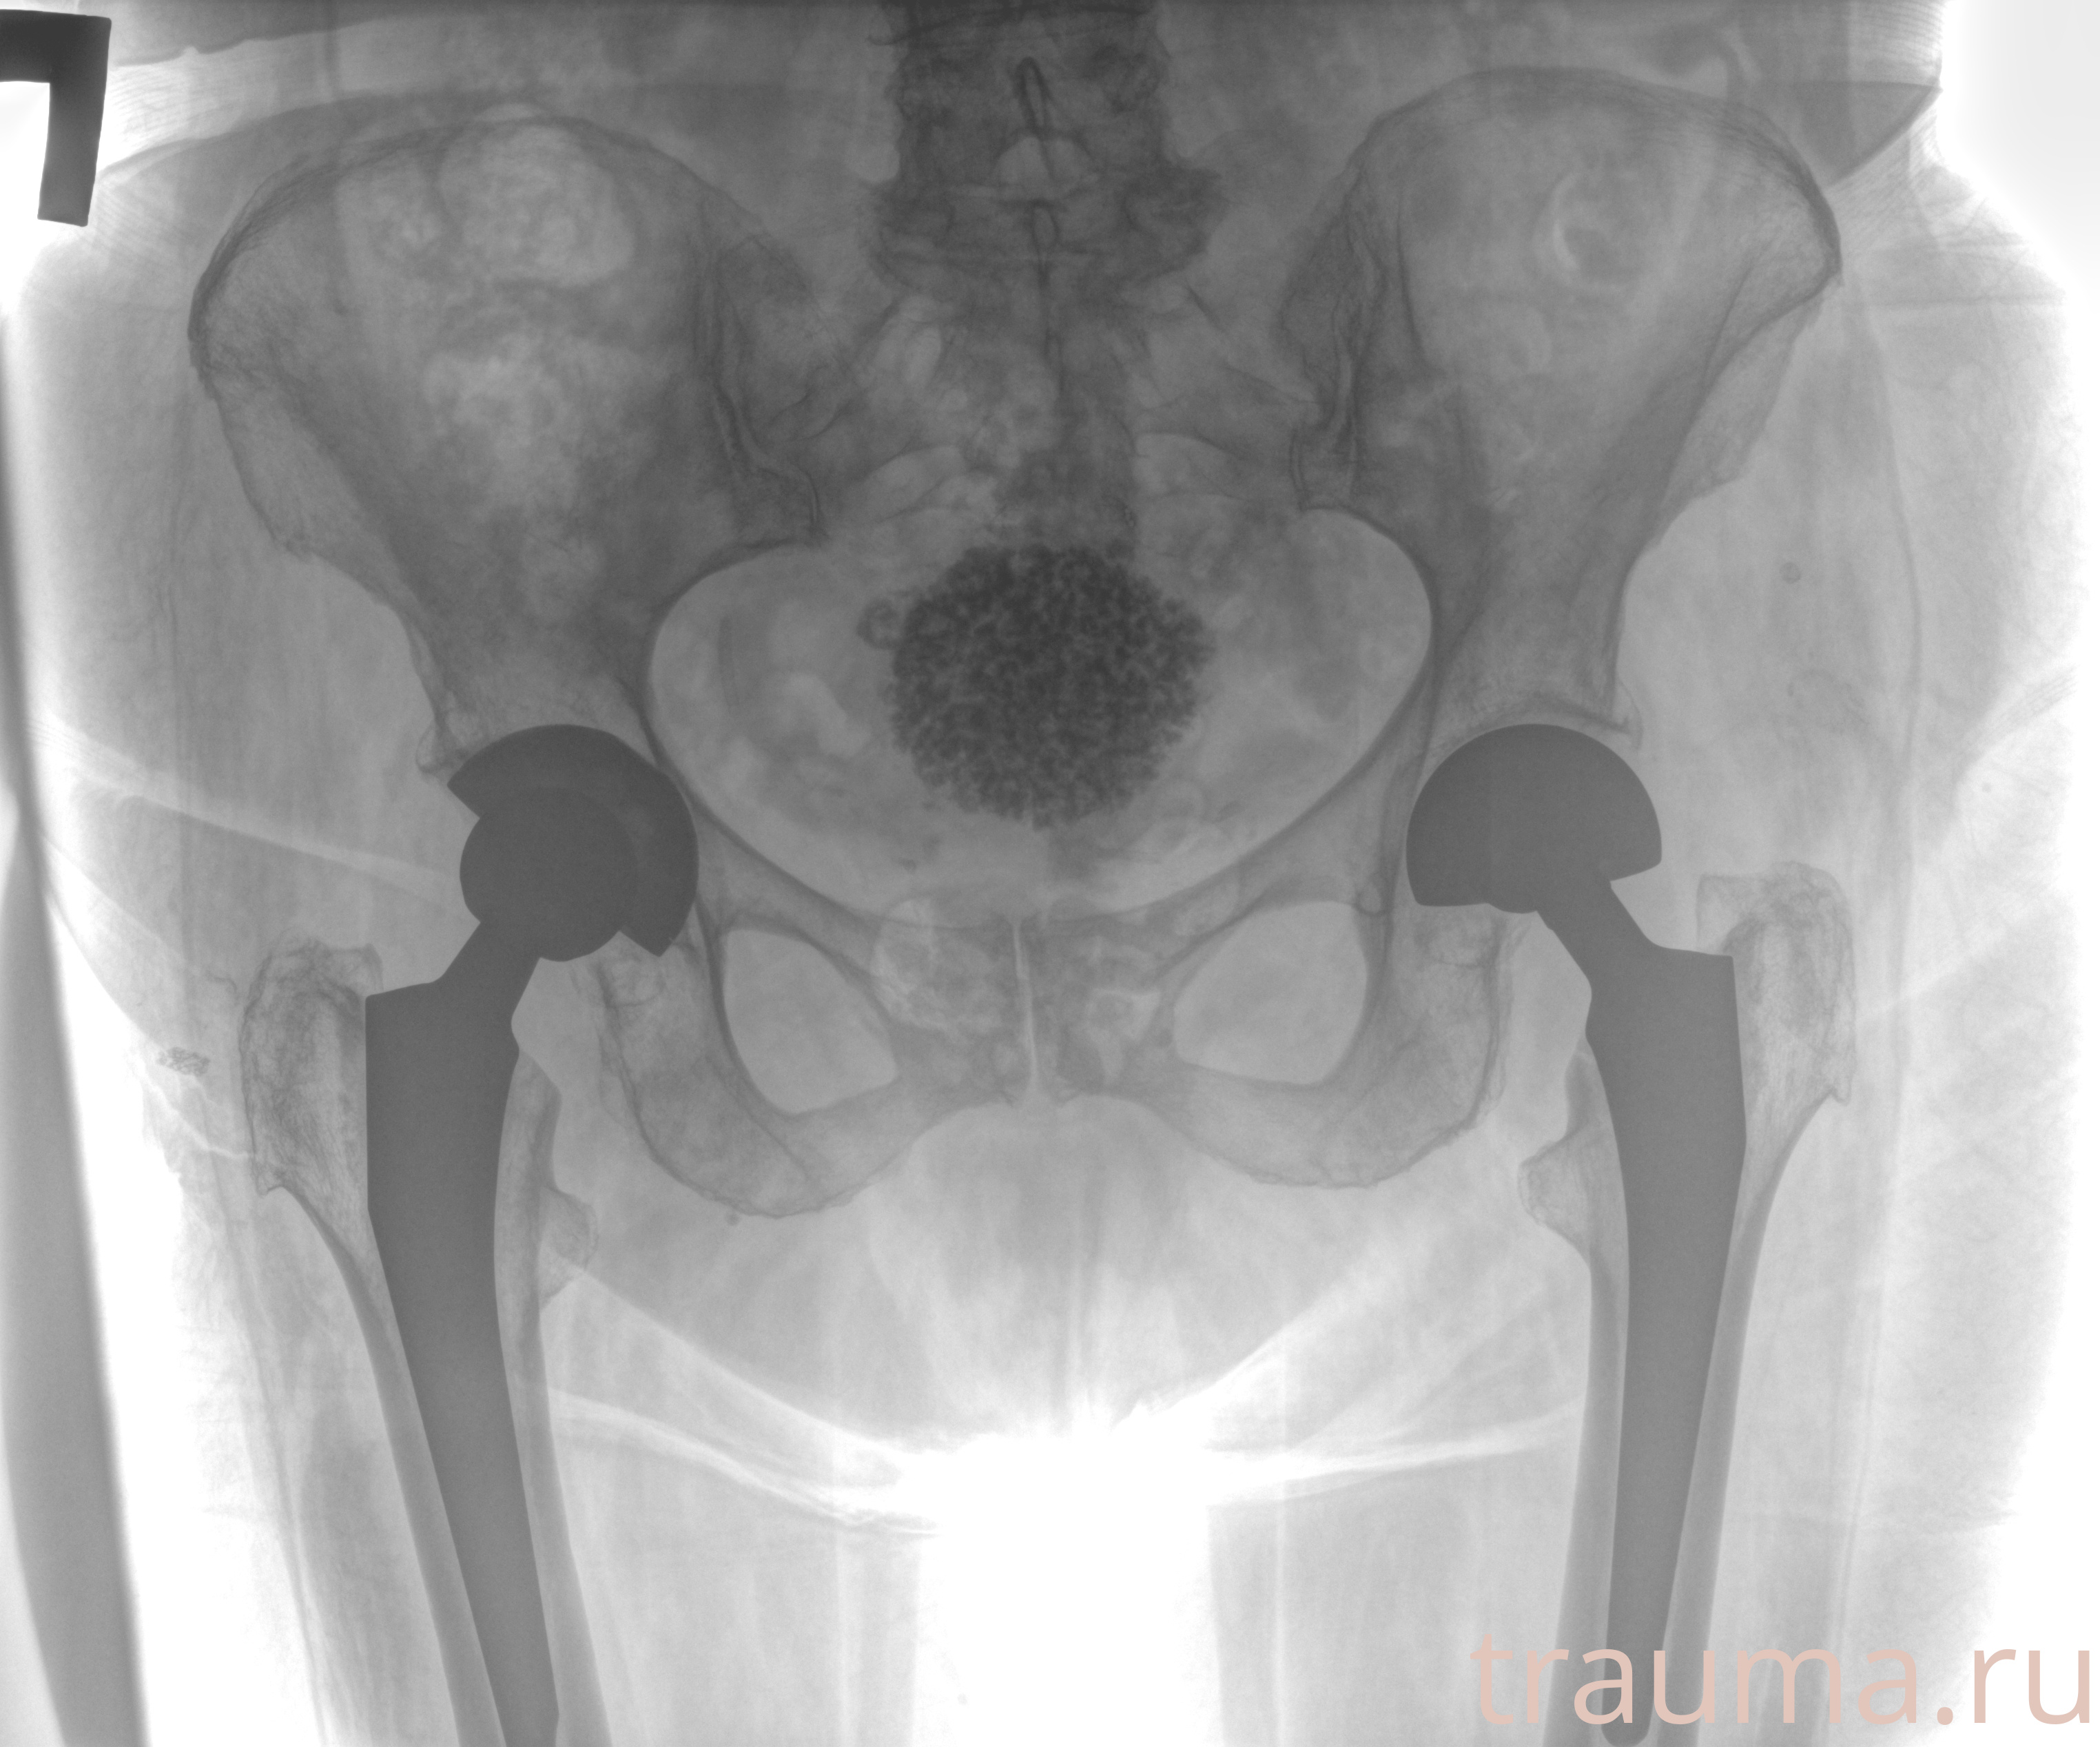

Рентгенограммы